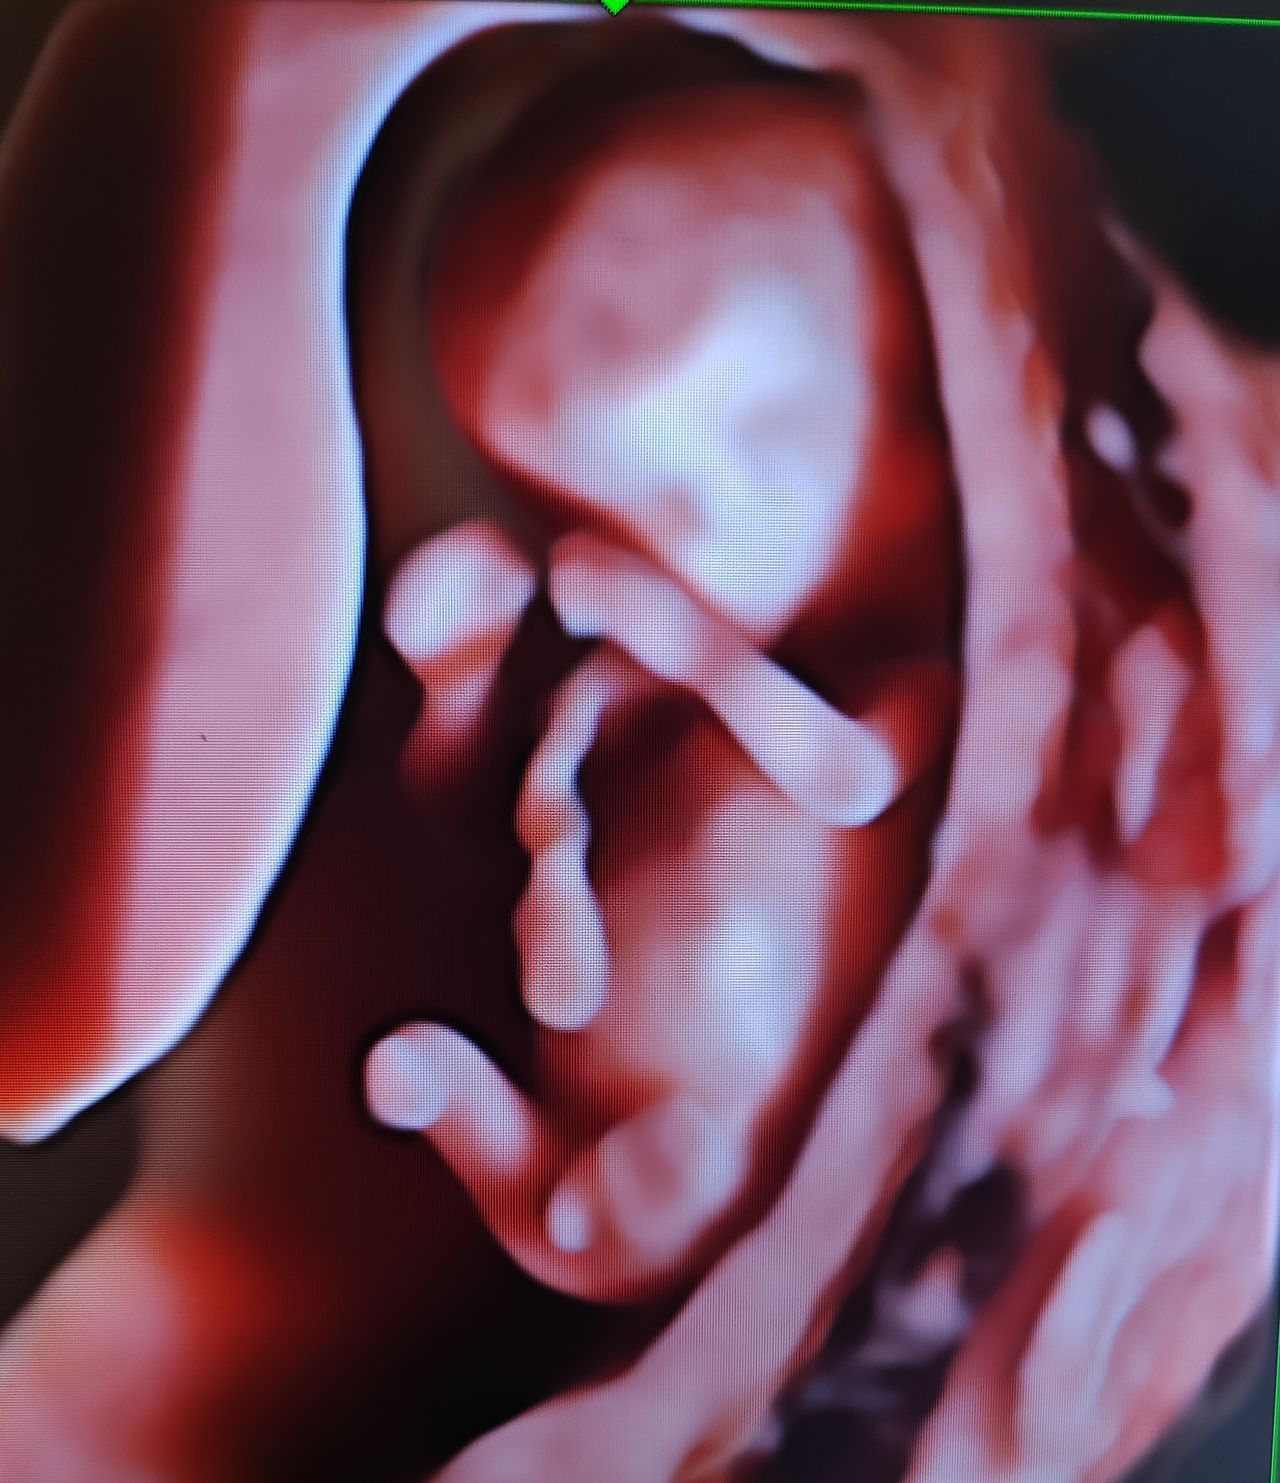

Dal 2015 al 2016 , frequenza presso U.O. Santa Maria delle Croci , Ravenna , periodo di Training di Chirurgia Laparoscopica, Endoscopica e di Isteroscopia ambulatoriale /office. In quell'anno nella stessa sede , ho  frequentato L'Ambulatorio di Diagnosi Prenatale acquisendo competenze in Ecografia Ostetrica del I-II-III trimestre.  Dopo la specializzazione ho proseguito la formazione e l'aggiornamento in particolare occupandomi dell’ Ecografia in ambito Ostetrico.

Ho acquisito "Certificate of Competence " da parte della Fetal Medicine Foundation per l'ecografia dell'11-13 settimana di gravidanza .

Da Maggio 2017 ad oggi faccio parte dello STAFF dell’Unità Operativa di Ostetricia e Ginecologia presso l’Ospedale "degli Infermi" di Faenza e dell’Ospedale "Morgagni Pierantoni "di Forli e mi occupo principalmente di Ostetricia , Gravidanza a Rischio, e dell'Ambulatorio Diagnosi Prenatale dove eseguo ecografie genetiche del I trimestre ed ecografie morfologiche e del III trimestre di gravidanza .